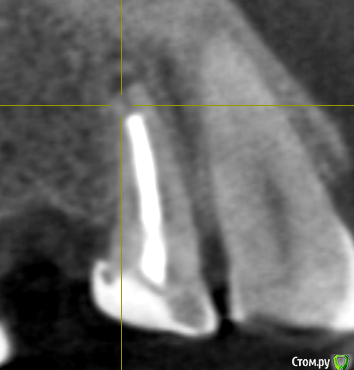

se77777 Опубликовано 19 декабря, 2019 Поделиться Опубликовано 19 декабря, 2019 (изменено) Здравствуйте, обнаружилась гранулема на 14.Предполагается имплантирование 15 и 46Предлагаются варианты для 14: удалить и поставить имплант или эндодентное лечение.Какой из этих вариантов выбрать? Спасибо. КТ https://yadi.sk/d/fcS6721v155x_Q Изменено 19 декабря, 2019 пользователем se77777 Ссылка на комментарий

se77777 Опубликовано 19 декабря, 2019 Автор Поделиться Опубликовано 19 декабря, 2019 Вопрос в целесообразности и вероятности успешного исхода эндодентного лечения. Ссылка на комментарий

red_butler Опубликовано 19 декабря, 2019 Поделиться Опубликовано 19 декабря, 2019 Вопрос в целесообразности и вероятности успешного исхода эндодентного лечения.лечение целесообразное, но гарантии не имеет, вероятность успеха высокая Ссылка на комментарий